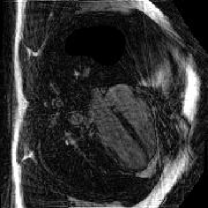

IV-C Compressive Sensing Dynamic MRI Reconstruction

The proposed method is tested on the retrospective cardiac cine dataset OCMR[53]. The detailed information of the dataset is listed in the supplementary file. The acquired data are transformed into the -space domain using the multi-channel NUFFT implementation with golden-angle radial trajectories based on Fibonacci number sequencing. Coil sensitivity maps are derived through the ESPRIT algorithm[54] to enable parallel imaging reconstruction. Different acceleration factors (AFs) are simulated for evaluation, including 21, 13, 8, 5, 3, 2, 1 spokes per frame (AF=9.7, 15.7, 25.5, 40.8, 67.9, 101.9, 203.7).

We select four representative baselines, including the NUFFT that provides direct zero-filled reconstructions without additional processing; the GRASP [39] that incorporates temporal frame grouping, time-averaged coil sensitivity estimation, and TV regularization; the FMLP [41] that employs INR and Fourier feature encoding for reconstruction; and the InstantNGP [24] that employs the multi-resolution hash grid encoding for dynamic MRI reconstruction.

IV-C2 Results

The quantitative results for compressive dynamic MRI reconstruction are shown in Table V. The proposed GridTD method outperforms competing methods across all evaluated settings in PSNR and SSIM metrics. Compared to other unsupervised deep learning methods FMLP and InstantNGP, our GridTD is over 50% faster due to the compact model structure. In Fig. 6, we present some visualizations of the reconstructed MRIs and the corresponding error maps, which demonstrate that GridTD better preserves structural edges and robustly recovers fine details, showing the superiority of our method for dynamic MRI reconstruction. All these results on video SCI, spectral SCI, and dynamic MRI reconstruction validate the strong performance of GridTD, positioning it as a versatile and state-of-the-art approach for compressive imaging reconstruction.